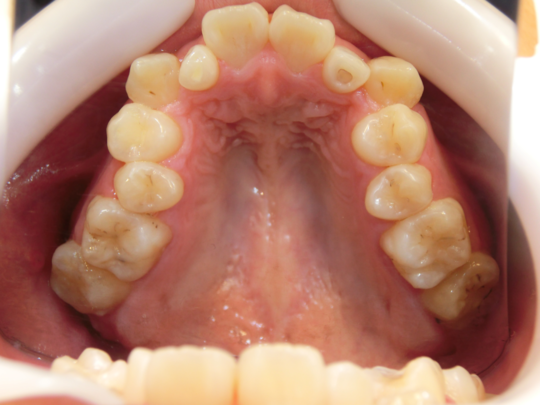

治療前

治療説明 歯科矯正でも目立ちにくい矯正方法であるマウスピース矯正で治療しました

治療期間 2年6か月

治療費用498000 円

治療後

治療の副作用(リスク)歯の動き方には個人差があり、予想された治療期間が延長する可能性があります。。マウスピースの使用状況、矯正歯科治療には患者さんの協力が必要であり、それらが治療結果や治療期間に影響します